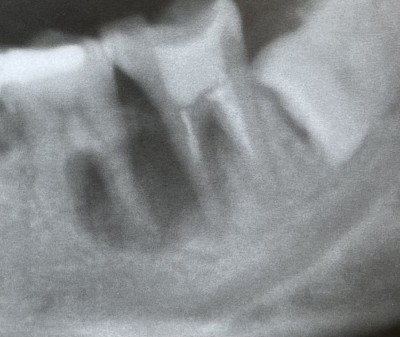

[下顎骨の骨折の3年経過】